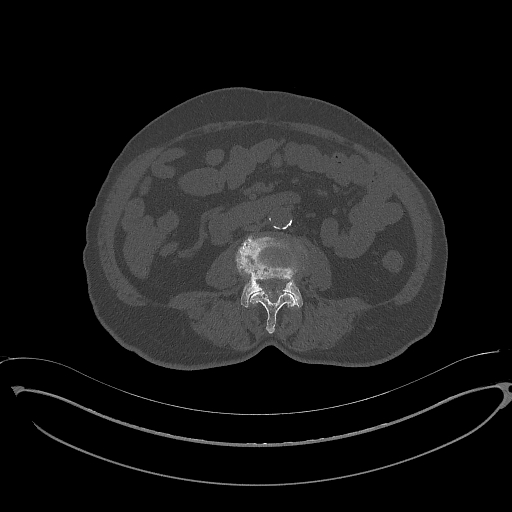

For the BM segmentation task, we compared the predicted masks generated by our approach with those from three competitive methods (Figure 5), which had proven to be the top performers, as shown in Table 3. These competitors include MISSFormer Huang et al. (2022), UCTransNet Wang et al. (2022a), and EDAUnet++ Afnouch et al. (2023). In the first two examples, we examined cases where Bone Metastasis had infected all bone regions within the slice. A closer inspection of the predicted masks revealed that most approaches were successful in highlighting the infected regions. However, it was evident that MISSFormer and EDAUnet++ struggled to capture segmentation details accurately. In contrast, our approach and UCTransNet excelled in matching the details present in the ground-truth masks. The remaining three examples represented slices where only a portion of the bone was infected by BM, which is a particularly challenging aspect of BM segmentation. In the third example, the comparison methods incorrectly segmented a part of the bone as a Bone Metastasis lesion. In contrast, our approach accurately matched the ground-truth mask in these scenarios. The last two examples demonstrated our approach’s ability to capture intricate lesion details effectively, showcasing the efficiency of our proposed compound encoder, which integrates Transformer and CNN features. In summary, the visualizations and comparisons reaffirm the effectiveness of our approach in BM segmentation, particularly in challenging cases, and highlight its ability to capture intricate lesion details efficiently.

Slice Bone Mask MISSFormer UCTransNet EDAUnet+ D-TrAttUnet GT

Figure 5: Visual Comparison of Bone Metastasis Segmentation Models Trained with Different Architectures.